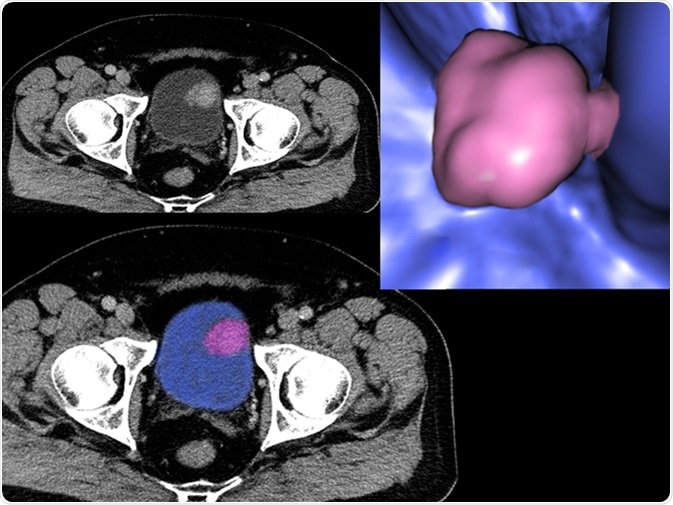

Image Credit: Semnic / Shutterstock